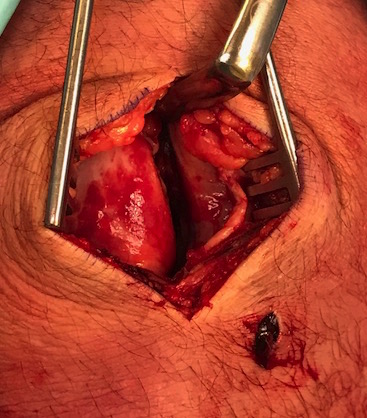

Open Technique

Very important to determine if torn from patella or medial epicondyle

1. Medical epicondyle avulsion

- over medial epicondyle

- divide deep fascia

- elevate VMO

- identify MPFL

- repair using bone anchors